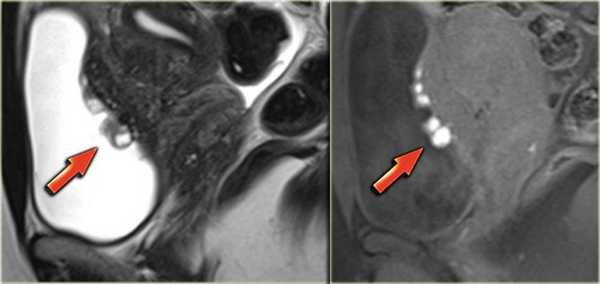

На Т2 взвешенных МР-томограммах определяются признаки эндометриоза с поражением стенки мочевого пузыря

На сагиттальных Т2 взвешенных МР-томограммах определяется поражение стенки мочевого пузыря на всю ее толщину, обусловленное эндометриозом, дающей изоинтенсивный сигнал по сравнению с мышцами; видны также гиперинтенсивные очаги, сопоставимые с расширенными эндометриальными железами. На Т1 взвешенной МР-томограмме с жироподавлением в зоне кровоизлияния визуализируются множественные мелкие кисты, дающие гиперинтенсивный сигнал